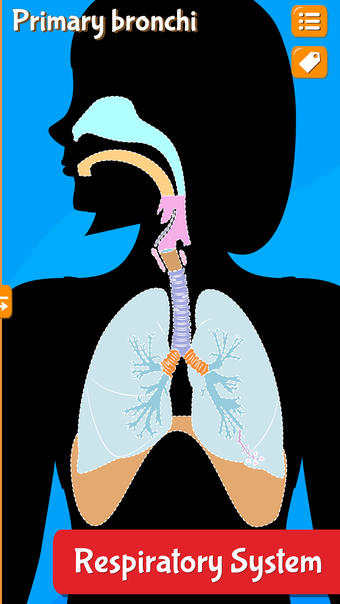

Anatomix es un juego de aprendizaje de anatomía humana que te enseñará a identificar todos los huesos del cuerpo humano y te permitirá explorar cada sistema en detalle. A medida que explores cada sistema, podrás identificar todos los huesos, músculos y otras estructuras.

Además de eso, podrás utilizar los diferentes huesos para identificar los diferentes sistemas.

La aplicación también te ayudará a identificar los diferentes huesos de tu propio cuerpo y te permitirá explorar cada sistema en detalle.